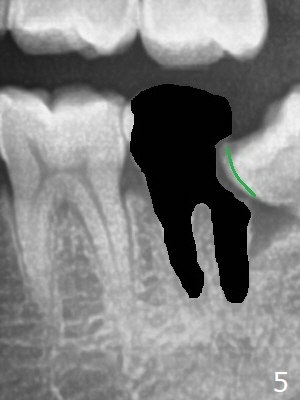

A 36-year-old man with poor dentition (smoker 1/4 ppd) requests extraction of sympto-matic teeth (#18 and 32, Fig.1). A half of Osteogen Plug is placed at #32 post extraction. To extract #18, the tooth has to be sectioned (Fig.2 red). The mesial portion is removed easy, while the distal one requires removing the mesial surface of #17 (Fig.2 green). Vanilla bone is placed after extraction (Fig.3), covered by 8x8 mm Amnion-Chorion Allograft and sutured with 4-0 PGA. Four months later, the mesial surface of #17 will be trimmed (Fig.4 black area) so that surgical guide metal sleeve (green) will be seated in the neutral position of the edentulous area. After extraction (Fig.5 black), the distal portion of the mesial crest will be resorbed, leading to gingival papilla atrophy and food impaction (Fig.6). Keeping the mesial portion of the root (Fig.7 *, socket shield) is able to prevent mesial crestal bone loss. The immediate implant will be placed ~ 2 mm short of the depth and checked whether it touches the retained root or not.